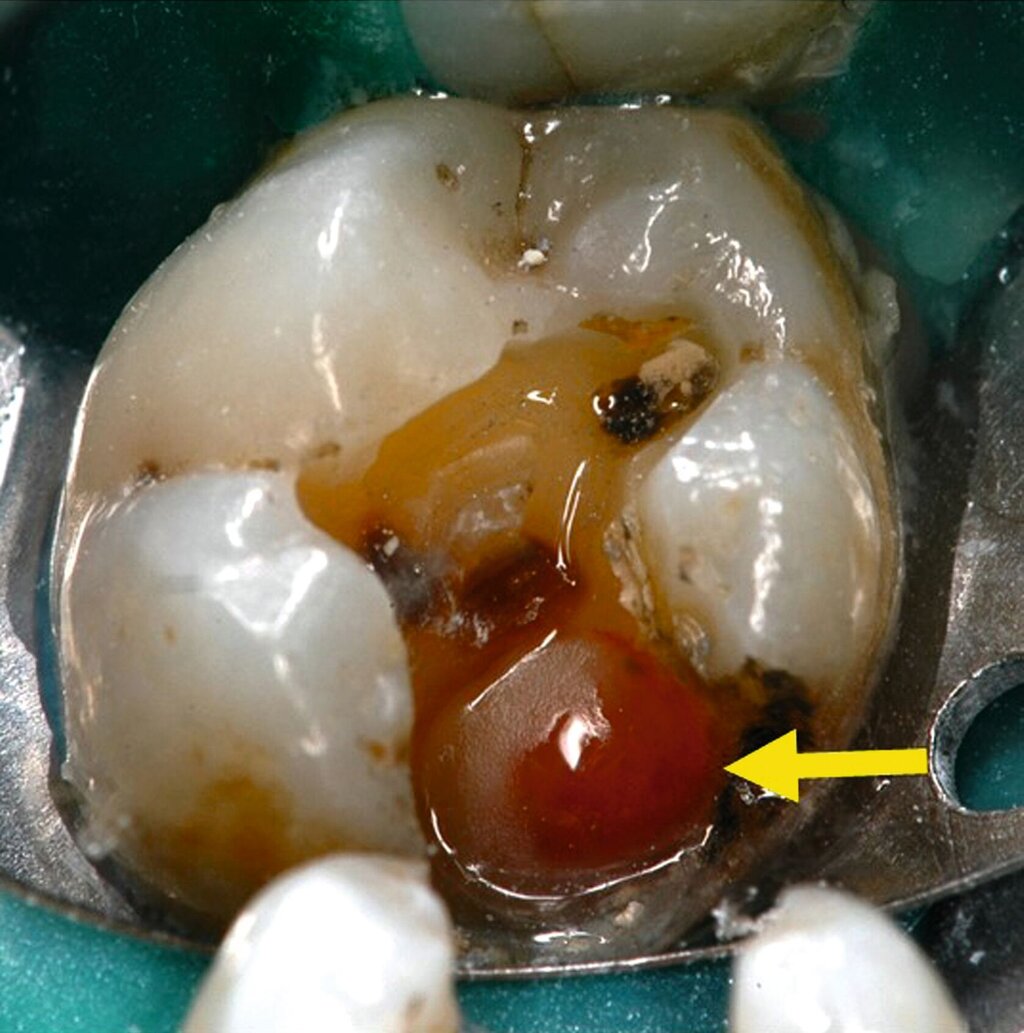

Lediglich eine klinische Symptomlosigkeit nach selektiver Kariesexkavation als Behandlungserfolg zu werten, ist daher zu kurz gedacht. Die klinischen Angaben der Patienten auf den Sensibilitätstest korrelieren möglicherweise nicht mit den histologischen Befunden. Histologisch sichtbare chronische Entzündungen, Mikroabszesse und Nekrosen nach selektiver Kariesexkavation können auftreten, ohne dass Patienten Beschwerden haben (Abbildungen 1a, b); das heißt, die Pulpa kann nach selektiver Kariesexkavation irreversibel entzündet sein, ohne dass dies vom Patienten bemerkt wird. Bei 81 von 224 Zähnen (36 Prozent) traten trotz partieller Nekrose der Pulpa und einer ausgeprägten Entzündungsreaktion keine Schmerzen auf [Langeland, 1959]. Trotz klinischer Beschwerdefreiheit und positiver Sensibilitätstestung fanden sich in allen der 12 untersuchten Zähne ein bis neun Monate nach selektiver Kariesexkavation histologisch Entzündungszellen in der Pulpa und Granulozyten in den afferenten Blutgefäßen [Ricucci et al., 2020] (Abbildung 2).

Aus all diesen Gründen empfehlen sowohl die Deutsche Gesellschaft für Endodontologie und zahnärztliche Traumatologie (DGET) als auch die Amerikanische Gesellschaft für Endodontie (AAE) in ihren aktuellen wissenschaftlichen Stellungnahmen zur Vitalerhaltung der Pulpa die vollständige Kariesexkavation. Nur dadurch ist es möglich, den tatsächlichen Zustand des Pulpagewebes klinisch zu beurteilen. Verbleibt kariöses Dentin am Kavitätenboden, behindert dies die Sicht auf mögliche Pulpaveränderungen wie Hyperämie oder Nekrosen (Abbildung 1). Auch besteht das Risiko, eine bereits bestehende minimale Freilegung der Pulpa zu übersehen, wenn eine dünne Schicht kariösen Dentins an der tiefsten Stelle der Kavität verbleibt. Wissenschaftlich lässt sich zudem eine höhere Erfolgswahrscheinlichkeit der derzeit propagierten selektiven Kariesexkavation gegenüber den vitalerhaltenden Maßnahmen nach Freilegung der Pulpa nicht feststellen [Dammaschke et al., 2019; AAE, 2021].